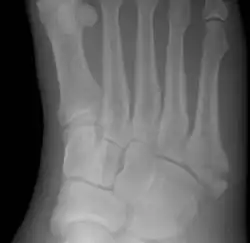

Jones fracture

| Jones fracture as seen on Xray | |

A Jones fracture is a broken bone in a specific part of the fifth metatarsal of the foot between the base and middle part .[8] In general, fifth metatarsal fractures heal readily, but a Jones fracture must be recognized and accurately diagnosed because of its higher rate of delayed healing or nonunion.[4] It results in pain near the midportion of the foot on the outside.[2] There may also be bruising and difficulty walking.[3] Onset is generally sudden.[4]

The fracture typically occurs when the toes are pointed and the foot bends inwards.[6][2] This movement may occur when changing direction while the heel is off the ground such in dancing, tennis, or basketball.[9][10] Diagnosis is generally suspected based on symptoms and confirmed with X-rays.[3]

Diagnostic X-rays include anteroposterior, oblique, and lateral views and should be made with the foot in full flexion.